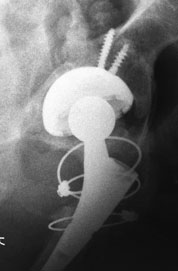

Уважаемые коллеги, помогите определиться!

На консультации женщина 64 лет.

Беспокоят ноющие боли по по передней поверхности правого тазобедренного

сустава около года. В течение последнего месяца боли усилились,

вынуждена пользоваться костылями. Оперирована пять лет назад в Испании.

Документов нет. Послеоперационный рубец, анализы, КТ–  без патологии.

Вопрос: что это за протез и нормально–  ли наличие такого«сочленения»  в

бедренном компоненте или это нарушение стабильности фиксатора?

С уважением, Юрий Алексеевич Булахтин